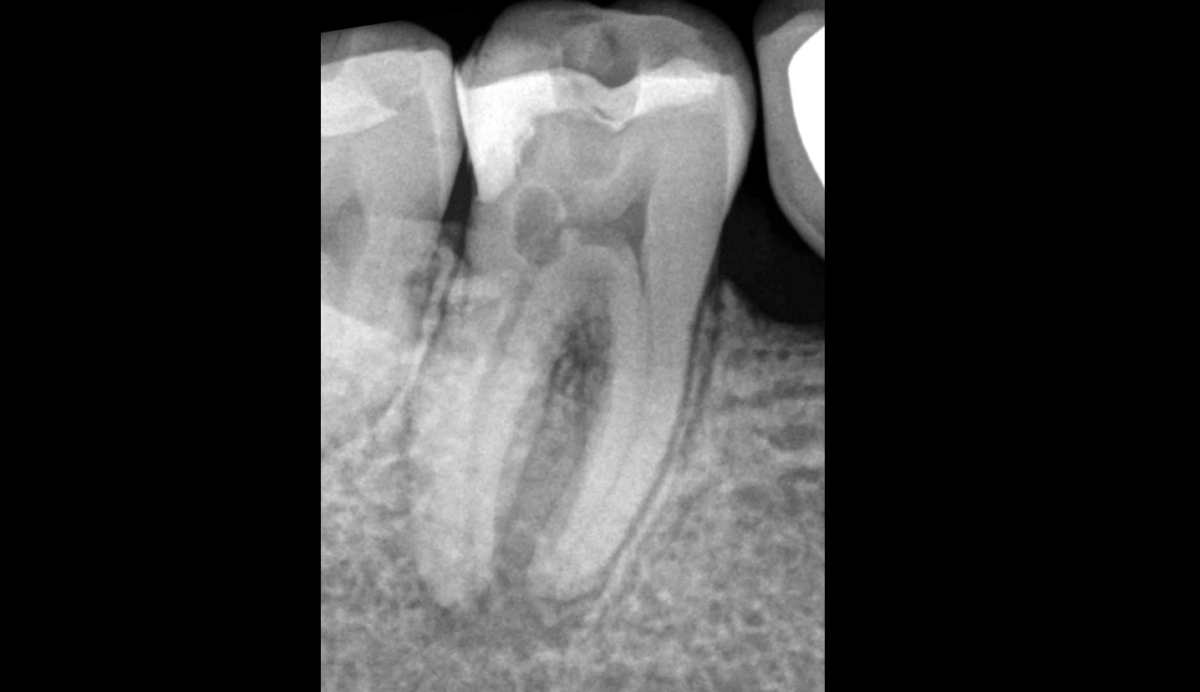

Catégories Non classé Cas de résorption radiculaire rare Auteur de l’article Par Dr Brice Riera Date de l’article 4 avril 2025 🔍 𝐂𝐚𝐬 𝐚𝐬𝐬𝐞𝐳 𝐫𝐚𝐫𝐞 𝐝’𝐮𝐧𝐞 𝐫𝐞́𝐬𝐨𝐫𝐩𝐭𝐢𝐨𝐧 𝐫𝐚𝐝𝐢𝐜𝐮𝐥𝐚𝐢𝐫𝐞 𝐢𝐧𝐭𝐞𝐫𝐧𝐞, située au niveau de la corne pulpaire distale de cette 47. ← Un retraitement canalaire nécessaire et suffisant ? → Congrès de l’Association Américaine d’Endodontistes 2025